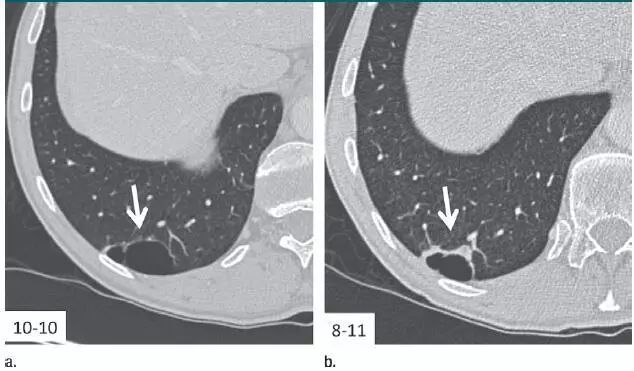

7. 相隔10个月的囊肿渐进表现

图 7 相隔 10 个月后进行的层厚 1 mm CT 横断面图像,显示右肺下叶囊肿壁渐进增厚的高度可疑模式(箭头)。手术证实为浸润性腺癌。